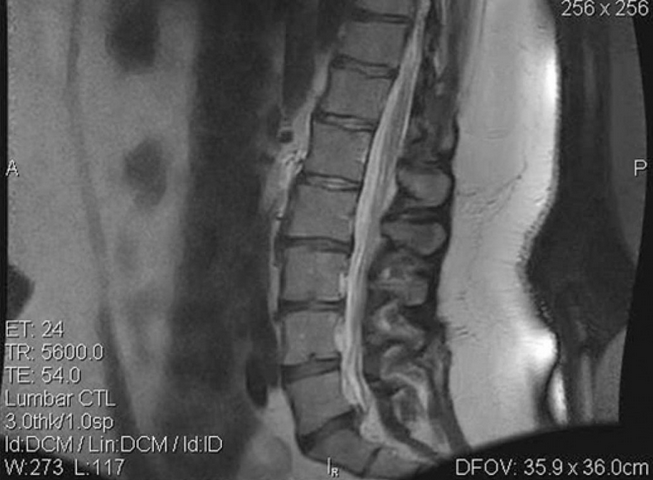

A 35-year-old female presented at an outpatient clinic in July 2006 complaining of LBP. The back pain was associated with numbness and recurrent right leg pain. The treating physician noted that the patient’s condition had been chronic since December 2004. These symptoms affected her ability to lift clients – a required part of her occupational duties – and were aggravated by sitting and prolonged standing. The patient weighed 291lb and was 5’ 8” tall. Her history was significant, with two motor vehicle accidents (in 1994 and 2002). Magnetic resonance imaging (MRI) of the lumbar spine performed on 19 July 2006 revealed a mild to moderate disc protrusion at L5/S1, eccentric to the right, impinging on the right S1 nerve root (see Figure 1). Mild degenerative changes with minimal bulging were also noted at L2/L3 and L3/L4. Upon initial examination, the patient presented limited lumbar range of motion (ROM), with pain in all planes, positive nerve root tension tests and decreased sensory and motor function of the right lower extremity.

Figure 1: Pre-treatment Magnetic Resonance Image